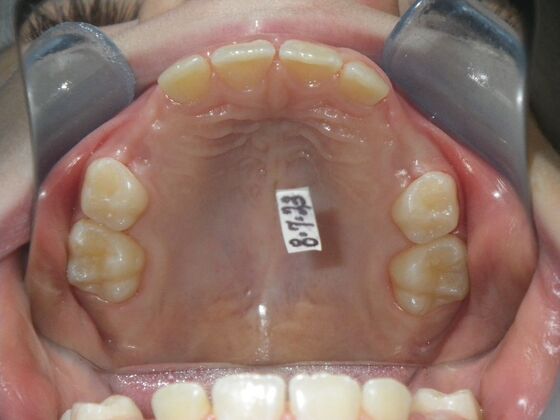

Patient presents with delayed eruption of the upper right central incisor and lower anterior crowding. Treatment plan to include exposure of right central incisor with bracket placement and correction of lower anterior crowding.